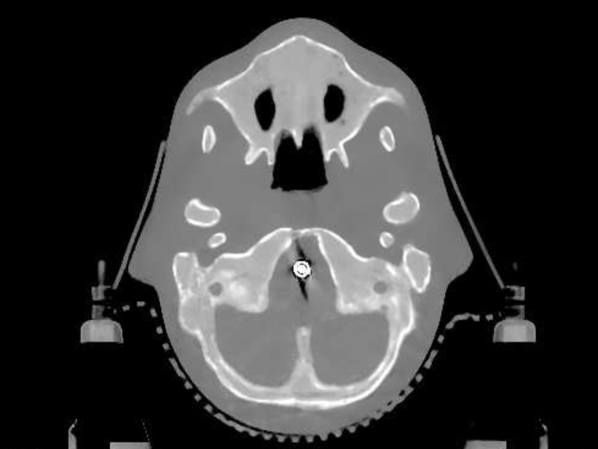

The data we used for our numerical reconstruction test were derived from the Adult Reference Computational Phantom (ICRP Publication 110,, 2009), which is a segmented image of defined density and chemical composition to represent real tissues. To investigate the ability to image metal implants, we inserted a pair of prosthetic hip joints (marked in green) with a solid titanium pin and shell. The slices through the chest and pelvis—which are the images we selected for testing—are shown in Figure 8. The resolution is 299×137299137299\times 137.

Refer to caption

(a) Chest test image

(b) Pelvis test image

Figure 8: Experimental data used: (a) is the oracle chest electron density; and (b) is the oracle pelvis electron density; both have a with display window of [0.8,1.2]